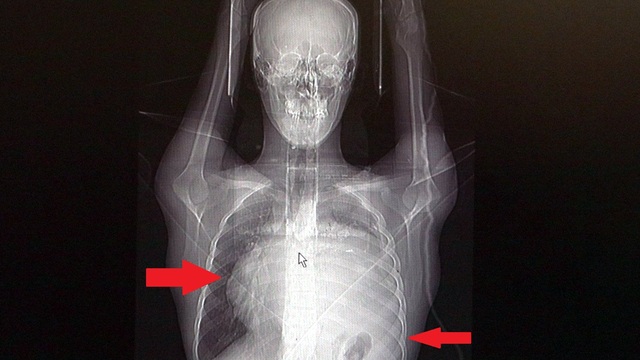

İstanbul'da yaşayan Burak Aktaş (21), Ağustos ayında halsizlik ve nefes darlığı şikayeti ile doktora gitti. Sol göğüs boşluğunda portakal büyüklüğünde bir kitle tespit edildi. İki seans kemoterapi gördü ama tedaviye rağmen tümör 2 ay içinde 8-10 kat büyüyerek karpuz boyutuna ulaştı. Kalbini göğüs boşluğunda 12 santimetre sağa iten, sol akciğerini neredeyse tamamen ezen dev tümör, Koşuyolu Yüksek İhtisas Eğitim ve Araştırma Hastanesi Göğüs Cerrahisi ve Kalp Damar Cerrahisi ekiplerinin beraber katıldığı büyük bir operasyonla başarıyla çıkarıldı. Bu kadar hızlı büyüyen kitle karşısında doktorları da şaşırdı.

İstanbul´da yaşayan 21 yaşındaki Burak Aktaş, Temmuz ayında işe girmek üzere sağlık raporu almak için hastaneye gitti. Herşey yolundaydı ve raporunu alarak iş başı yaptı. Bir ay geçmeden nefes darlığı, halsizlik, öksürük gibi şikayetlerle başka bir hastaneye gittiğinde ise ilk şoku yaşadı. Sol göğüs boşluğunda portakal büyüklüğünde bir kitle tespit edilmişti. Yapılan biyopside tümörün akciğer kaynaklı olmadığı, henüz cenin aşamasında eşey hücrelerinin farklılaşmasıyla gelişen "immatür teratom" teşhisi kondu. Kitleyi küçültmek için kemoterapi uygulansa da tam tersine tümör 2 ay içinde neredeyse 10 katına çıktı ve büyük bir karpuz boyutuna ulaştı. Sol akciğerinin yüzde seksenini kağıt gibi ezen, kalbini göğüs duvarında 12 santim sağa kaydıran ve hem kalbe hem beyne giden ana damarlara baskı yapan 6.5 kilo ağırlığındaki dev tümör, Koşuyolu Yüksek İhtisas Eğitim ve Araştırma Hastanesi Göğüs ve Kalp Damar Cerrahisi ekiplerinin birlikte girdiği operasyonla başarılı şekilde çıkarıldı. Operasyon sırasında Aktaş´ın kalbi normal yerine çekildi, sol akciğerin üst lobu alındı, ezilen alt lobu ise anestezi ekipleri tarafından pozitif basınçla yeniden şişirildi. Ameliyatı gerçekleştiren ekipten Prof. Dr. Erdal Taşçı, Aktaş´ın göğüs boşluğunun neredeyse tamamını kaplayan 6,5 kiloluk tümörün teratom (eski Yunancada `canavar tümör´) türlerinden biri olduğunu ve embriyonik hücrelerden kaynaklandığını kaydetti.

Prof. Dr. Erdal Taşçı, "Bundan 2,5-3 ay öncesine kadar hiçbir problemi olmayan, hayatını normal devam ettiren bir delikanlı Burak. Göğüs ağrısı öksürük ve nefes darlığı şikayetiyle sağlık kuruluşuna başvuruyor. Orada yapılan tetkiklerinde sol göğüs boşluğunda akciğerinden kaynaklanmayan portakal büyüklüğünde bir kitle tespit ediliyor ve immatür teratom tanısı konuyor. 2 ay arayla yapılan tetkiklerinde ve arada cerrahi öncesi küçültme amaçlı kemoterapi almasına rağmen, portakal büyüklüğündeki tümör, irice bir karpuz büyüklüğüne, yaklaşık 6 kilo 300 grama kadar ulaşıyor. Göğüs boşluğunda kemik kafesi içinde olduğu için, itebileceği iki organ var; biri kalp, diğeri de akciğerler. Soldan sağa doğru büyüdüğü için kalbi tamamen göğüs boşluğunun sağ tarafına itmiş ve kalbe giren ve kalpten çıkan bütün büyük damarları da yer değiştirmenin etkisiyle bükülmüş durumdaydı. Bu nedenle vücuduna yeterince kan gitmiyordu. Ağustos ayının başında portakal büyüklüğündeyken kitle Eylül sonuna irice bir kavun, Ekim ayına geldiğimizde ise bir karpuz büyüklüğüne ulaştığı için, kitlenin büyüme hızı bizi acilen ameliyat yapmaya yöneltti. Yaklaşık 8-10 kat hacimsel olarak artmıştı. Sol akciğer tamamen ezilmiş ve kağıt haldeydi, alt lobu anestezi ekibimiz yüksek basınç uygulayarak tekrar şişirdi. Çok fazla vaktimiz yoktu, kitle basısından dolayı yaşamla bağdaşmayacağından dolayı hızlı hareket etmek zorundaydık. Bize geldikten üç gün sonra hemen ameliyata aldık çünkü tümörden ziyade onun yaptığı baskıdan kaynaklı hayati riski vardı" dedi.

Normalde kalbin özellikle alt ucunun göğüs boşluğunda, iman tahtası orta çizgi kabul edilirse, sola bakar şekilde durduğuna dikkat çeken Prof. Dr. Taşçı, sözlerini şöyle sürdürdü: "Ama bu hastada yaklaşık 12-13 s santimlik kalbin alt ucununu yer değiştirmesi ve kalbe giren çıkan bütün damarlar bükülüp kan akımı bozulmuştu. Kalp Damar Cerrahisi ekibi de bizimle beraber ameliyata girdi. Sol akciğerin üst lobu artık geri dönüşümsüz olarak ezildiği için çıkarmak zorunda kaldık. Kalbi tekrar eski pozisyonuna getirdik. Ameliyat sonrası çok çabuk toparladı. Koşuyolu ailesi olarak böyle büyük bir vakanın altından başarıyla çıktığımız için de ayrıca çok gururluyuz. Bundan sonra onkolog arkadaşlarımız hastamızın yaşamına çok olumlu dokunuşlar yapacak. İmmatür teratom genelde embriyojenik çağda gelişim gösteren germ hücrelerinin farklılaşmasıyla büyür. Vücudun herhangi bir yerinde gelişebilir ve içinde saç, diş, kemik artıkları, jölemsi kıvamda maddeler bulundurabilen bir tümör çeşididir. Kombine tedavilerde çok iyi sonuçlar alınıyor. Bu çocuğumuzu ileride güzel bir hayat bekliyor."